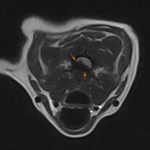

体の何処かを痛がるとの事でダックスさんがかかりつけ医を受診したところ、椎間板ヘルニアではないか?との頃で精査のため来院されました。エックス線検査とMRIでC2~C3に脊髄圧迫病変が確認されました。Ventral Slotで脊柱管内に逸脱した椎間板物質を摘除しました。速やかに除痛効果が現れています。